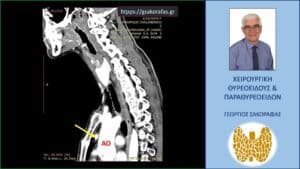

Ενδοθωρακικό αδένωμα παραθυρεοειδούς (έκτοπο). Αξονική τομογραφία – διατομή σε προσθιοπίσθιο επίπεδο. Το αδένωμα (κίτρινο βέλος) απεικονίζεται έμπροσθεν της μεσότητας της ανιούσης αορτής (ΑΟ), λίγο πάνω από την έκφυσή της.